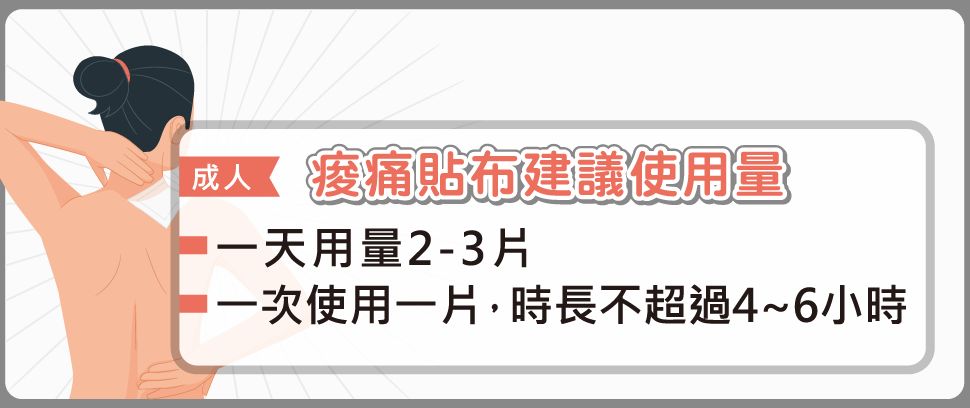

筋骨痠痛貼布,過量恐傷肝腎!

當您覺得腰痠背痛時,第一個想到的是貼痠痛藥布嗎?根據復健醫學會調查,國人每月平均使用6片藥布,每年總使用量超過4億3,800萬片。但您知道痠痛貼布使用不當或使用過量,可能產生副作用、甚至傷肝腎嗎?